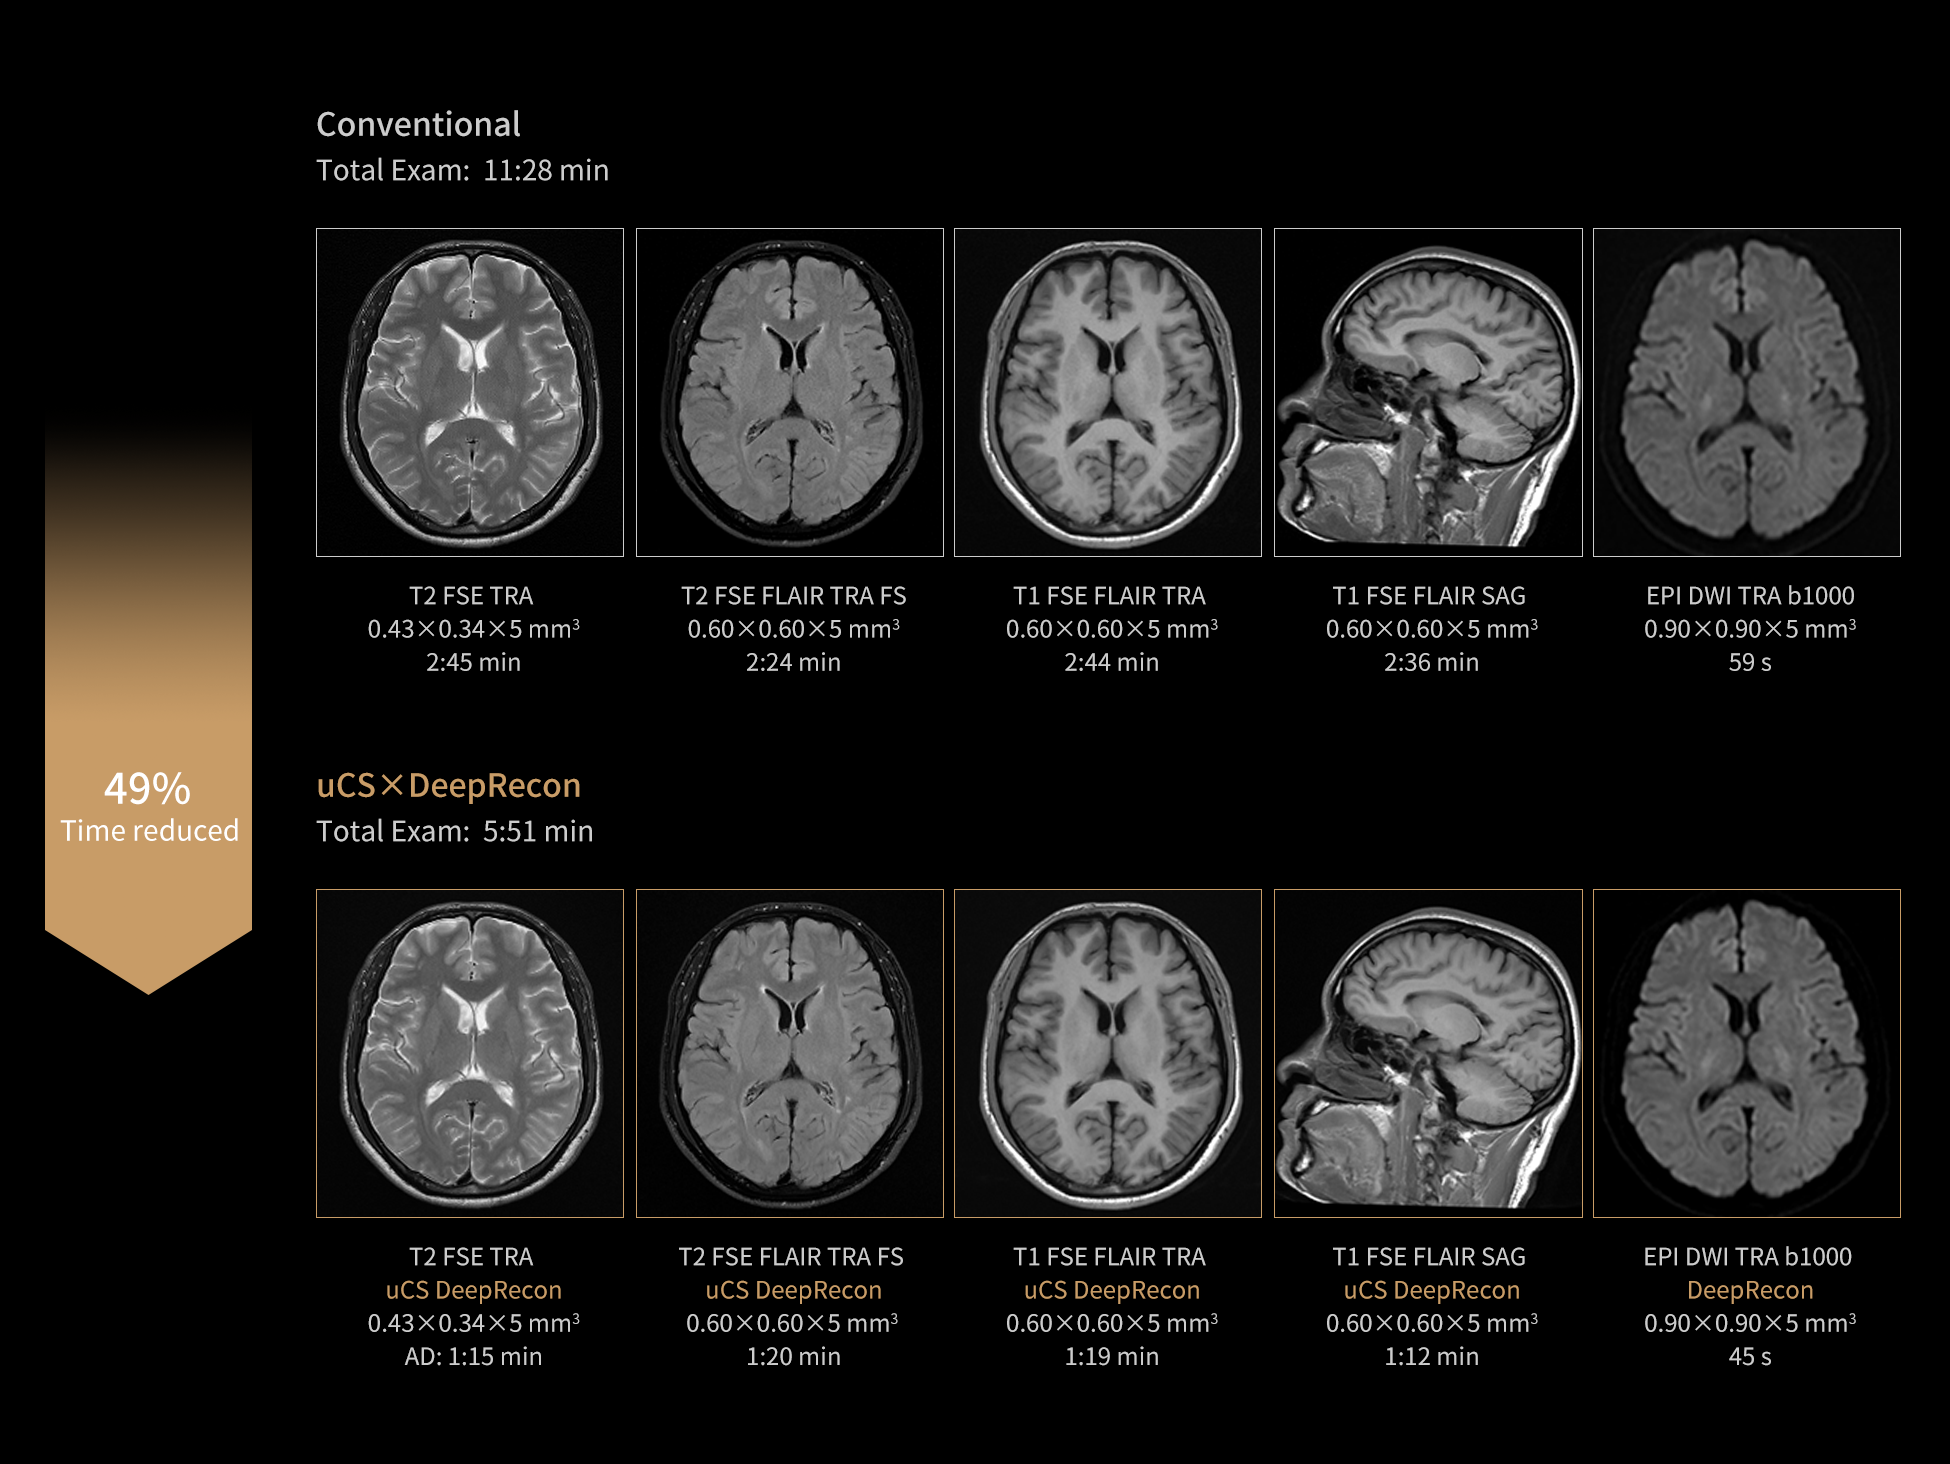

uMR 670 is a new breed of MRI that is EASY to have an efficient exam. Powered by the unparalleled AI-based image reconstruction technology DeepRecon and acceleration technology uCS, uMR 670 boosts SNR and image sharpness to near-3T levels—all while cutting scan time. Experience 1.5T performance, reimagined.

DeepRecon is a cutting-edge deep learning-based image reconstruction technology, unlocking a new era of image quality and speed. Based on a deep learning-based image reconstruction algorithm, DeepRecon enables intelligent denoising for improved signal-to-noise ratio, while simultaneously increasing image sharpness. It supports all body parts with a broad range of sequences, enabling rapid and confident diagnoses.

The state-of-the-art uCS technology, featuring high-speed acquisition. With an extensive array of imaging sequences (including 3D and 2D)—it effectively addresses diverse clinical applications across all body parts.

Maintain image quality with shorter scan times. Our advanced denoising algorithms and high resolution MRI technology are precisely customized to deliver confident diagnose for vital exams and optimize productivity.

Using the same protocol, DeepRecon is capable of significantly enhancing the signal-to-noise ratio (SNR) and providing rich image details.